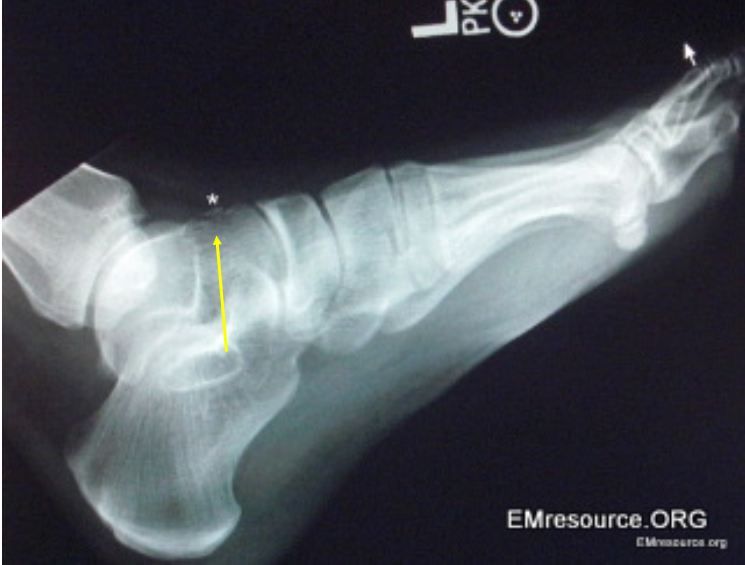

Figure. Note lesion at arrow. Click to enlarge.

There is a subtle fracture on the superior part of the anterior talus. See Figure, above, and note area at point of arrow.Please click image to enlarge. Discussion

The talar avulsion fracture in this patient is also small with only slight displacement and is seen hovering just above the mid to anterior talus. Treatment usually includes a period of immobilization followed by gradual return to activity. Crutches are advised initially. Avulsion fractures tend to do well and require less aggressive treatment than fractures through the body of the talus.